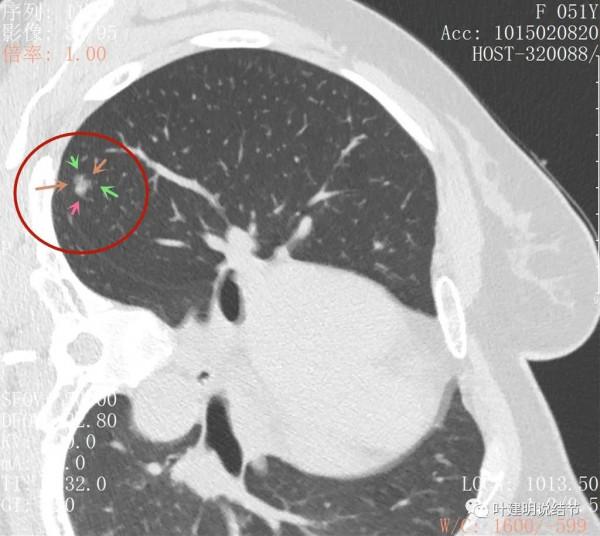

主病灶此層是磨玻璃,但有明顯血管進入病灶(桔色箭頭)

病灶表現不平,密度雜亂,輪廓相對清楚

有明顯的分葉徵(磚色箭頭)以及磨玻璃成分(綠色箭頭)和偏實性的成分(粉紅色箭頭)

上圖也示病灶有明顯的分葉徵(磚色箭頭)以及磨玻璃成分(綠色箭頭)和偏實性的成分(粉紅色箭頭)